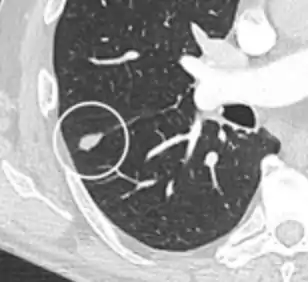

- Margin morphology: a spiculated margin is a risk factor for cancer.[8] Benign causes tend to have a well defined border, whereas lobulated lesions or those with an irregular margin extending into the neighbouring tissue tend to be malignant.[10] In particular, spiculations are highly predictive of malignancy with a positive predictive value up to 90%.[9] Also, a "notch sign", which is an abrupt indentation of the nodule, increases the risk of cancer, but may also be found in granulomatous diseases.[9]

Round well-delineated solid lung nodule with smooth border.[9]